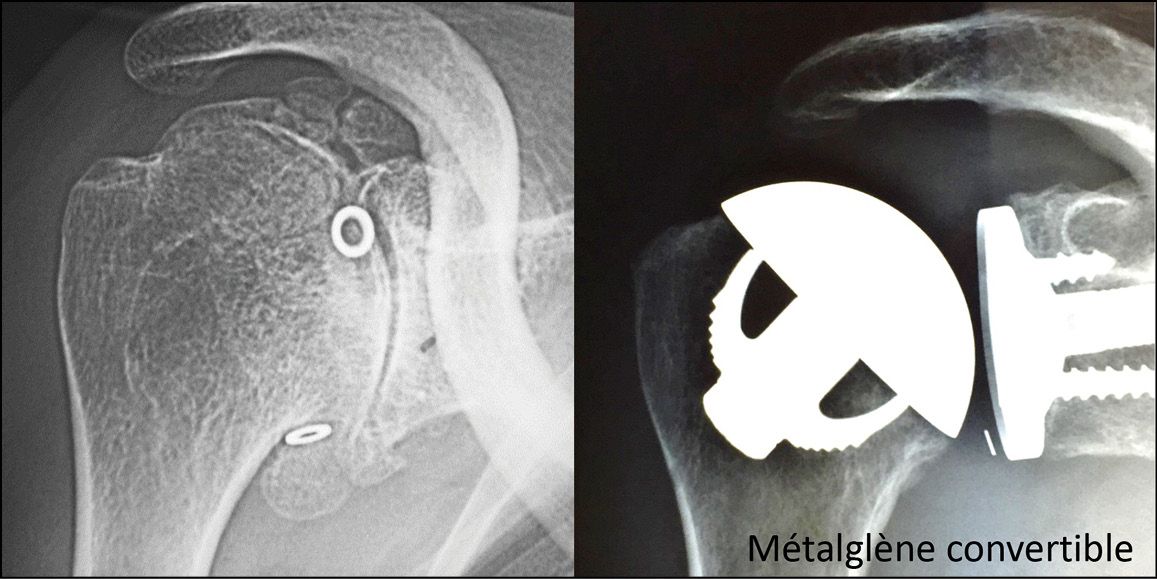

The designers used version 1 of the TESS Implant, which had a modular and convertible design, for a total of 105 procedures throughout 2003, then assessed the results the following year (Fig. 1). In 2005, version 2 of the definitive TESS system was launched (Fig. 2). Thanks to satisfactory clinical outcomes at 5 years, [1] Huguet D, Declercq G, Rio B, Teissier J, Zipoli B. Results of a new stemless shoulder prosthesis: Radiologic proof of maintained fixation and stability after a minimum of three years follow-up. J Shoulder Elbow Surg 2010; 19, 847-852 most companies gradually began including a stemless design in their implant range.

This was followed by a second wave of stemless implants that could be converted for use in both anatomical and reverse procedures: the Easytech from FX Solutions in 2012, the Nano Biomet in 2013, and the SMR S from Lima in 2014 (Fig. 5).